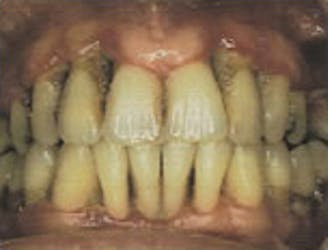

Advanced Periodontitis

- Teeth may become mobile or loose

- Constant bad breath and bad taste

- Roots may be exposed and teeth are sensitive to hot and cold

- Severe horizontal and angular bone loss on x-ray

- Pockets between teeth and gums are 6mm or deeper